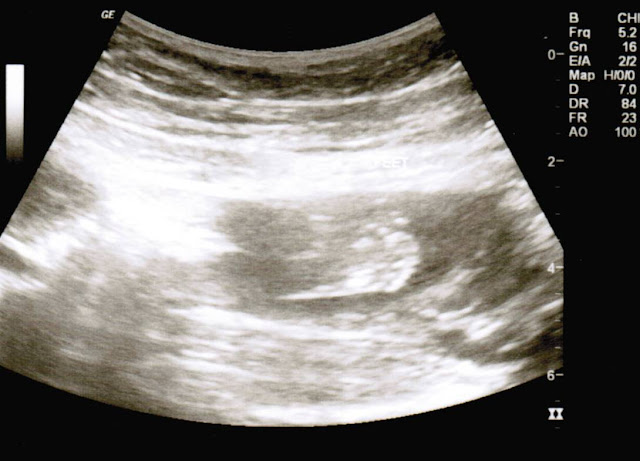

The ultrasound tech told us that our little one looks perfect, is about 10 ounces, and has a very strong heartbeat of 153 beats per minute. She also mentioned that I have an anterior placenta which explains why I haven't felt the baby move yet. [Click here to find out what an anterior placenta is] Hopefully within the next few weeks though I'll be able to feel our little one - I cannot wait until I do!! :)

| Our little one's spine and head. His/her arms were crossed and in front of the face. |

| A close-up of the face |

| The feet |

| The baby was facing down and all snuggled up. :) |